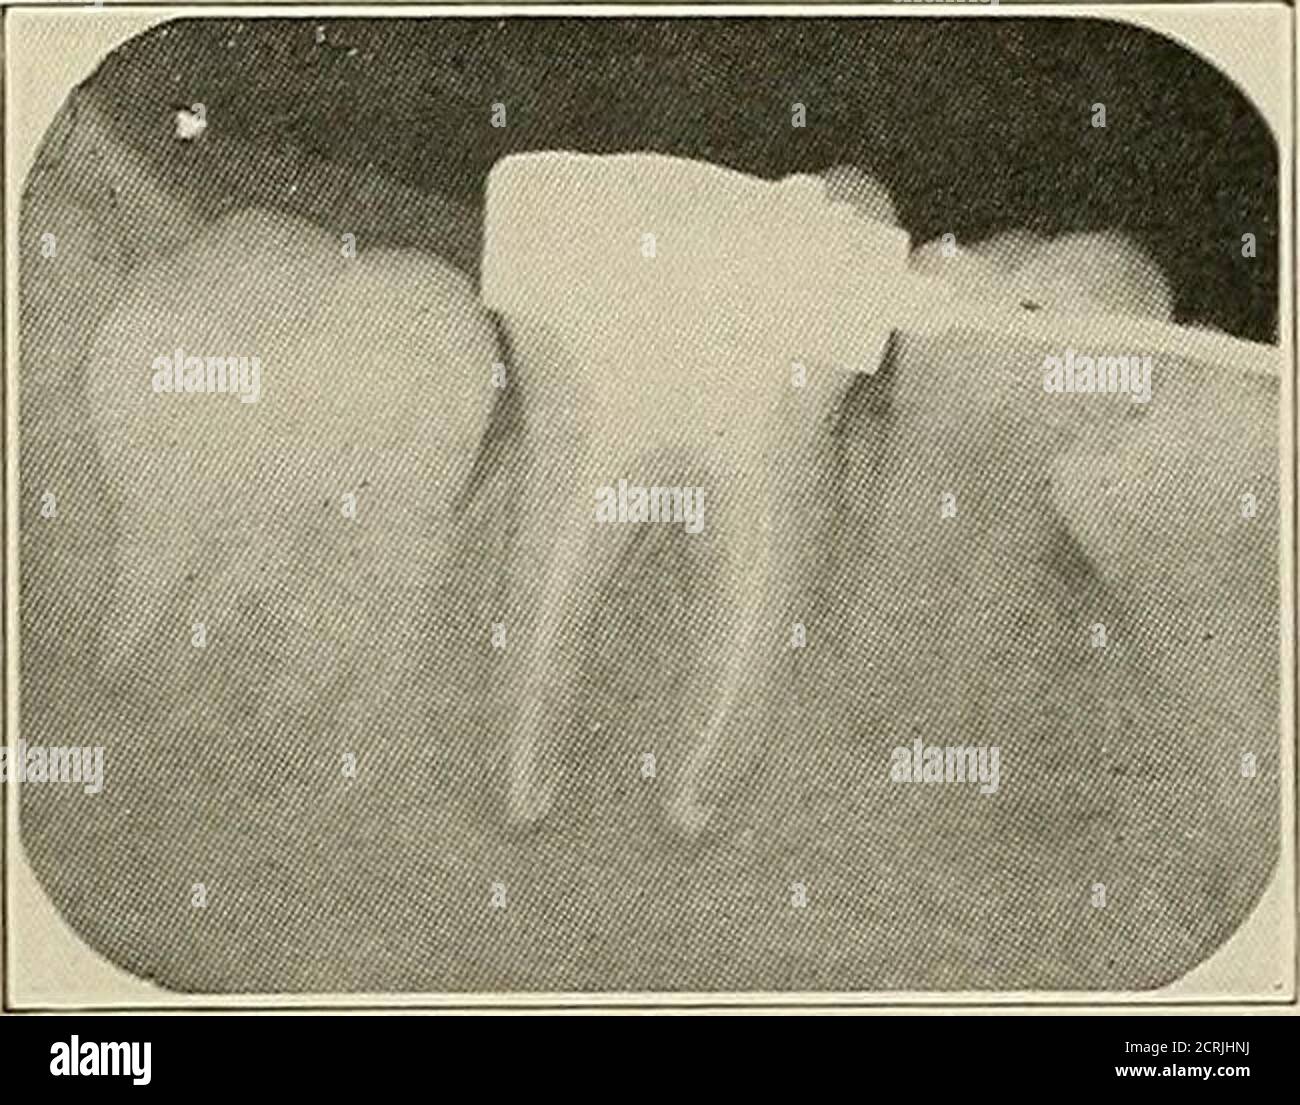

From www.alamy.com

Examples Of Dental Radiography High Resolution Stock Photography and Pa Dental Radiology Requirements going forward, in accordance with section 11.4 of the dental law, 63 p.s. this section cited in 49 pa. Code § 33.1 (relating to definitions); § 130e, any individual who has passed the board’s. dentistry board resources and documents. the state board of dentistry regulates the practice and licensure of dentists, dental hygienists, and the certification. Pa Dental Radiology Requirements.